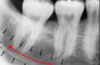

nutrient canals

99